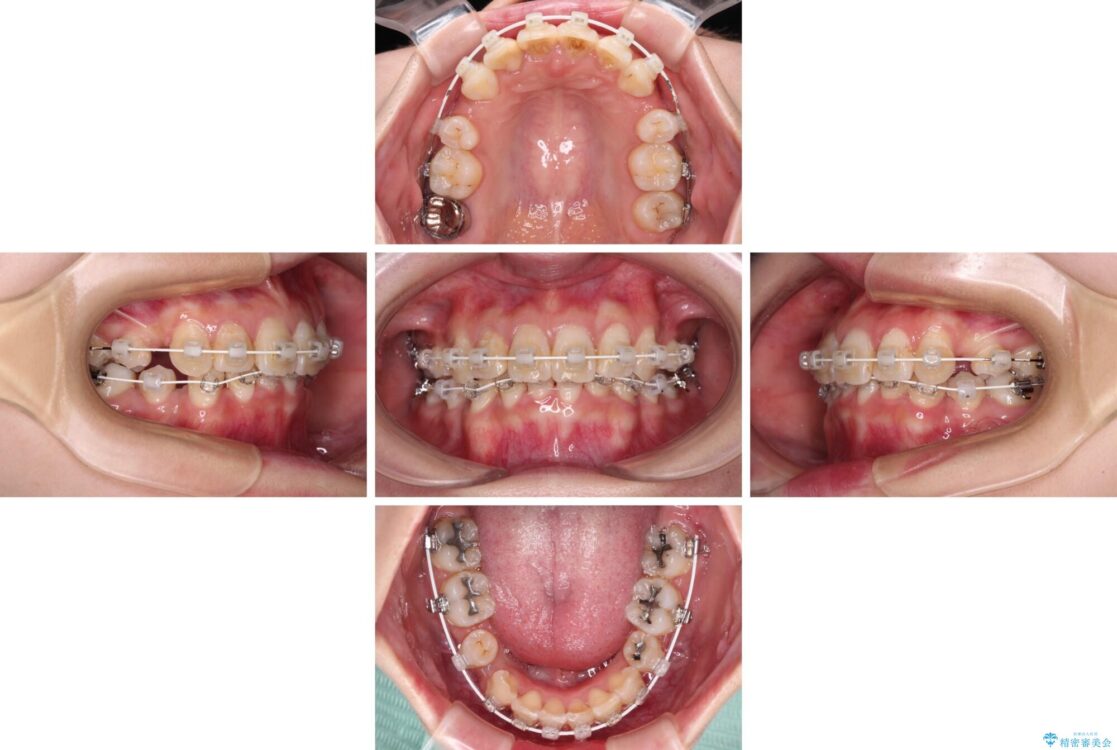

下顎の叢生を解消するために抜歯が必要であり、奥歯の咬み合わせや口元の印象から、上顎も同様に抜歯と判断し、上下左右の第1小臼歯4本抜歯してワイヤー装置にて矯正治療を行うこととしました。

咬み合わせが深く、そのままでは上顎の抜歯スペースが閉じきらない可能性があったため、治療初期から深い咬み合わせを改善させるように試みました。

実際にはなかなか改善されず、当初予定よりも治療期間がやや長期化してしまいました。

治療途中

• デコボコと深い咬み合わせ ワイヤー装置での抜歯矯正 治療途中画像